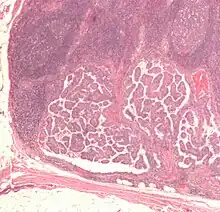

The cells in a metastatic tumor resemble those in the primary tumor. Once the cancerous tissue is examined under a microscope to determine the cell type, a doctor can usually tell whether that type of cell is normally found in the part of the body from which the tissue sample was taken.

For instance, breast cancer cells look the same whether they are found in the breast or have spread to another part of the body. So, if a tissue sample taken from a tumor in the lung contains cells that look like breast cells, the doctor determines that the lung tumor is a secondary tumor. Still, the determination of the primary tumor can often be very difficult, and the pathologist may have to use several adjuvant techniques, such as immunohistochemistry, FISH (fluorescent in situ hybridization), and others. Despite the use of techniques, in some cases the primary tumor remains unidentified.